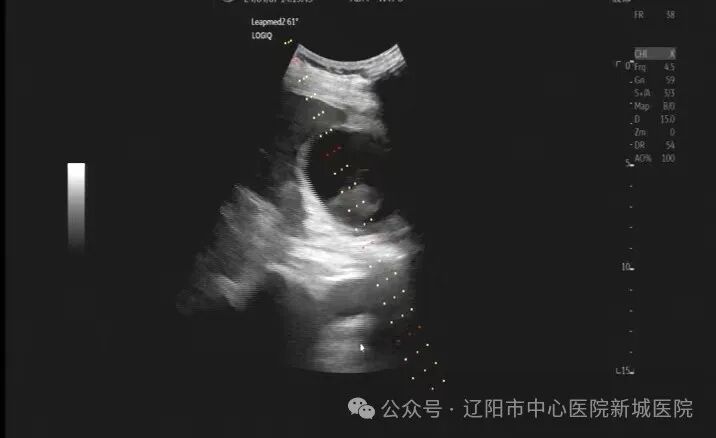

老人的各项生命指标经过积极治疗,病情趋于平稳,于是在入院第六日,由超声科张雅丽主任和刚玉恩主任为老人在超声引导下行经皮经肝胆囊置管引流术,手术当日引流褐色胆汁 80 毫升;术后第二日引流黄绿色胆汁100毫升,老人生命体征平稳,精神状态良好;术后第三日老人带管出院回家。